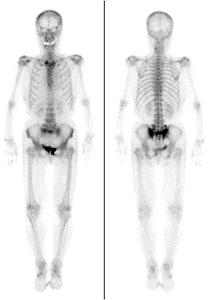

PET検査はがんの診断において優れた検査です。また、脳の機能をみることによって、認知症や神経疾患の詳しい検査を行うことができます。

当センターでは、2017年3 月末に日本で3 番目となる半導体PET/CT GEDiscovery MI が導入されました( 図PET1)。2013 年6 月に新施設の開設と同時に導入されたGE Discovery PET/CT 710(図PET2)と合わせて高性能PET/CT が2台となります。

今まで運用されていたPET/CT 710 に関しても、time-of-flight などの先進的な技術が使われ、高性能でありますが、今回導入された機種は、光電子増倍管の代わりに半導体を使用し、今までよりも約2 倍の感度を誇る最新鋭の機種です。

当センターでは毎週月曜日と金曜日に保険診療のPET-CT 検査を行っております。心臓サルコイドーシスにも保険適応が拡充されましたが、絶食時間の条件が異なりますので、その場合にはご連絡をしてください。

FDG PET-CT は、早期胃がんを除く悪性腫瘍の病期診断に保険適応があります。

検査自体は低侵襲のため高齢者や様々な合併症を抱える患者様にも安全に検査が受けられます。最新のPET/CT により一層近隣の先生方の診療や地域の皆様の健康にお役に立てればと思います。